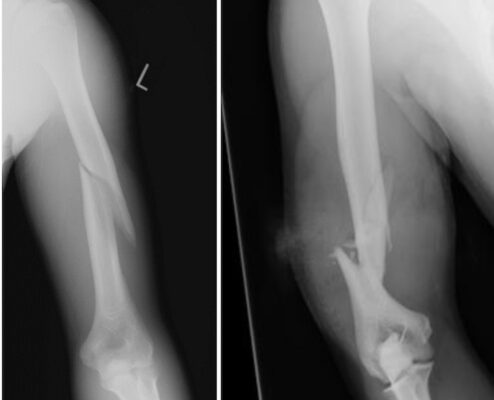

- Chẩn đoán hình ảnh ban đầu được thực hiện là chụp X quang thường xương cánh tay, thẳng và nghiêng.

Các dạng gãy có thể được phân loại theo phân loại OTA hoặc mô tả dạng đứt gãy.

Phân loại theo mô tả:

- Vị trí gãy: một phần ba trên, giữa hoặc dưới

- Kiểu gãy: ngang, chéo, xoắn, nhiều mảnh